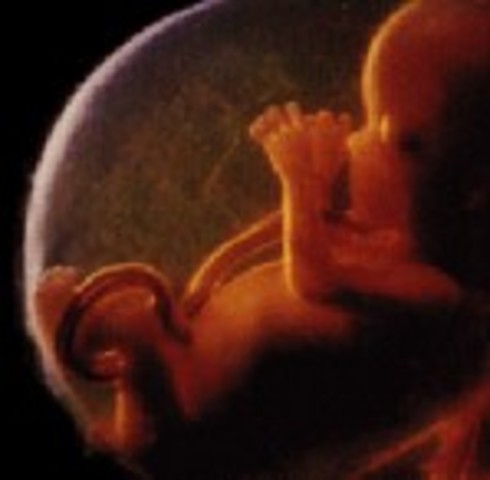

• Week 26 end of second trimester

Week 26 end of second trimester

The baby is more responsive to touch, and the babies muscles become more coordinated and it starts moving around in the womb. The baby has the ability to suck it's thumb which strengthen the jaw muscles, at this time the baby is 14 inches long and weighs around 1.7 pounds.

Fact: you can play with the baby by touching on your stomach